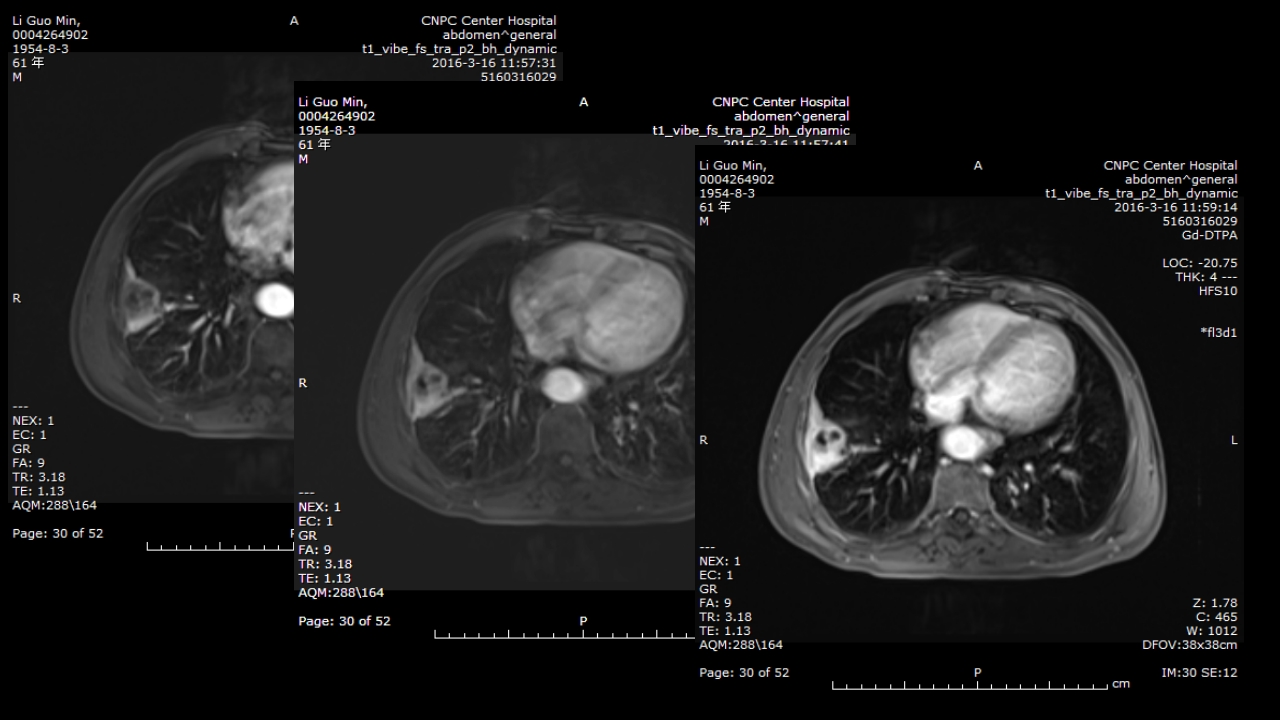

肺部肿块有效的影像检查选择